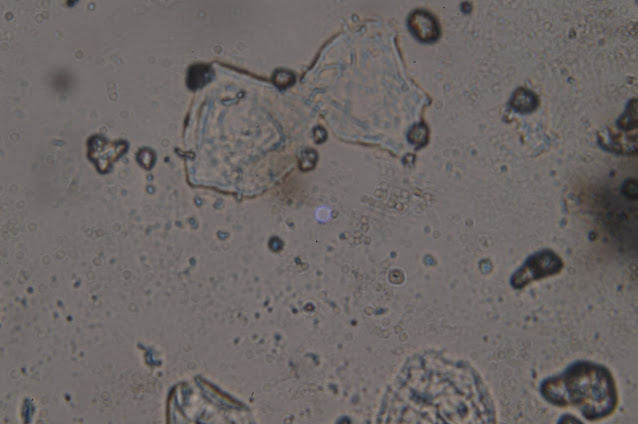

ここでは、もう少し拡大して見ることができます。

これは、インフルエンザに対する、Vaxigripワクチンの小瓶からのものであることを思い出してください。インフルエンザワクチンの話です。ここでは、もう少し拡大してみました。光学顕微鏡のコンデンサーによって、明るさが異なります。

リカルド・デルガド:ここを見てください、これはさらに拡大しています。

リカルド・デルガド:これはとても特徴的ですよね。

そして、ここではもっと拡大しています。

サンプルは左が昨年のあのVaxigripのインフルエンザワクチン、20209月・10月のものです。そして右は、別のコンデンサーで、科学文献に描かれているような酸化グラフェンを見ることができます。つまり、左のサンプルに見られるように、ひだがあり、いくつかの層が重なっています。右の写真と同じような特徴があり、ひだやエッジが折り重なっているのがわかります。非常によく似ています。このナノ材料を扱っている人や、光学顕微鏡や電子顕微鏡で見たことがある人に聞いてみると、「これも酸化グラフェンだ」と言われました。どうですか?これが20209月・10月のインフルエンザワクチン「Vaxigrip」です。